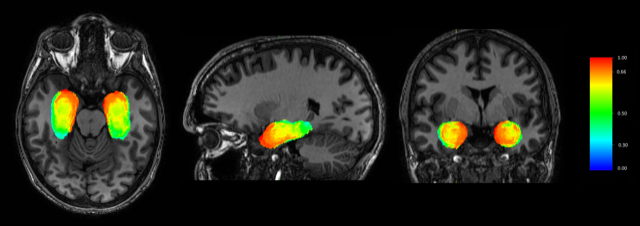

The study is also the first to assess impact of the surgical technique of laser ablation on outcomes in these patients, using a unique imaging approach. “We hope that the model we developed can help advise surgeons in their surgical planning and approach, thereby improving results for these patients even further,” said Pierre-François D'Haese, Research Assistant Professor of Electrical Engineering at Vanderbilt University, in a statement. D’Haese is also the chief executive officer of Neurotargeting, LLC, which led the development of CranialCloud, a unique HIPAA-compliant, social-network-like platform that allowed each of the members of this study to share clinical data in a virtual, de-identified environment to conduct the study.